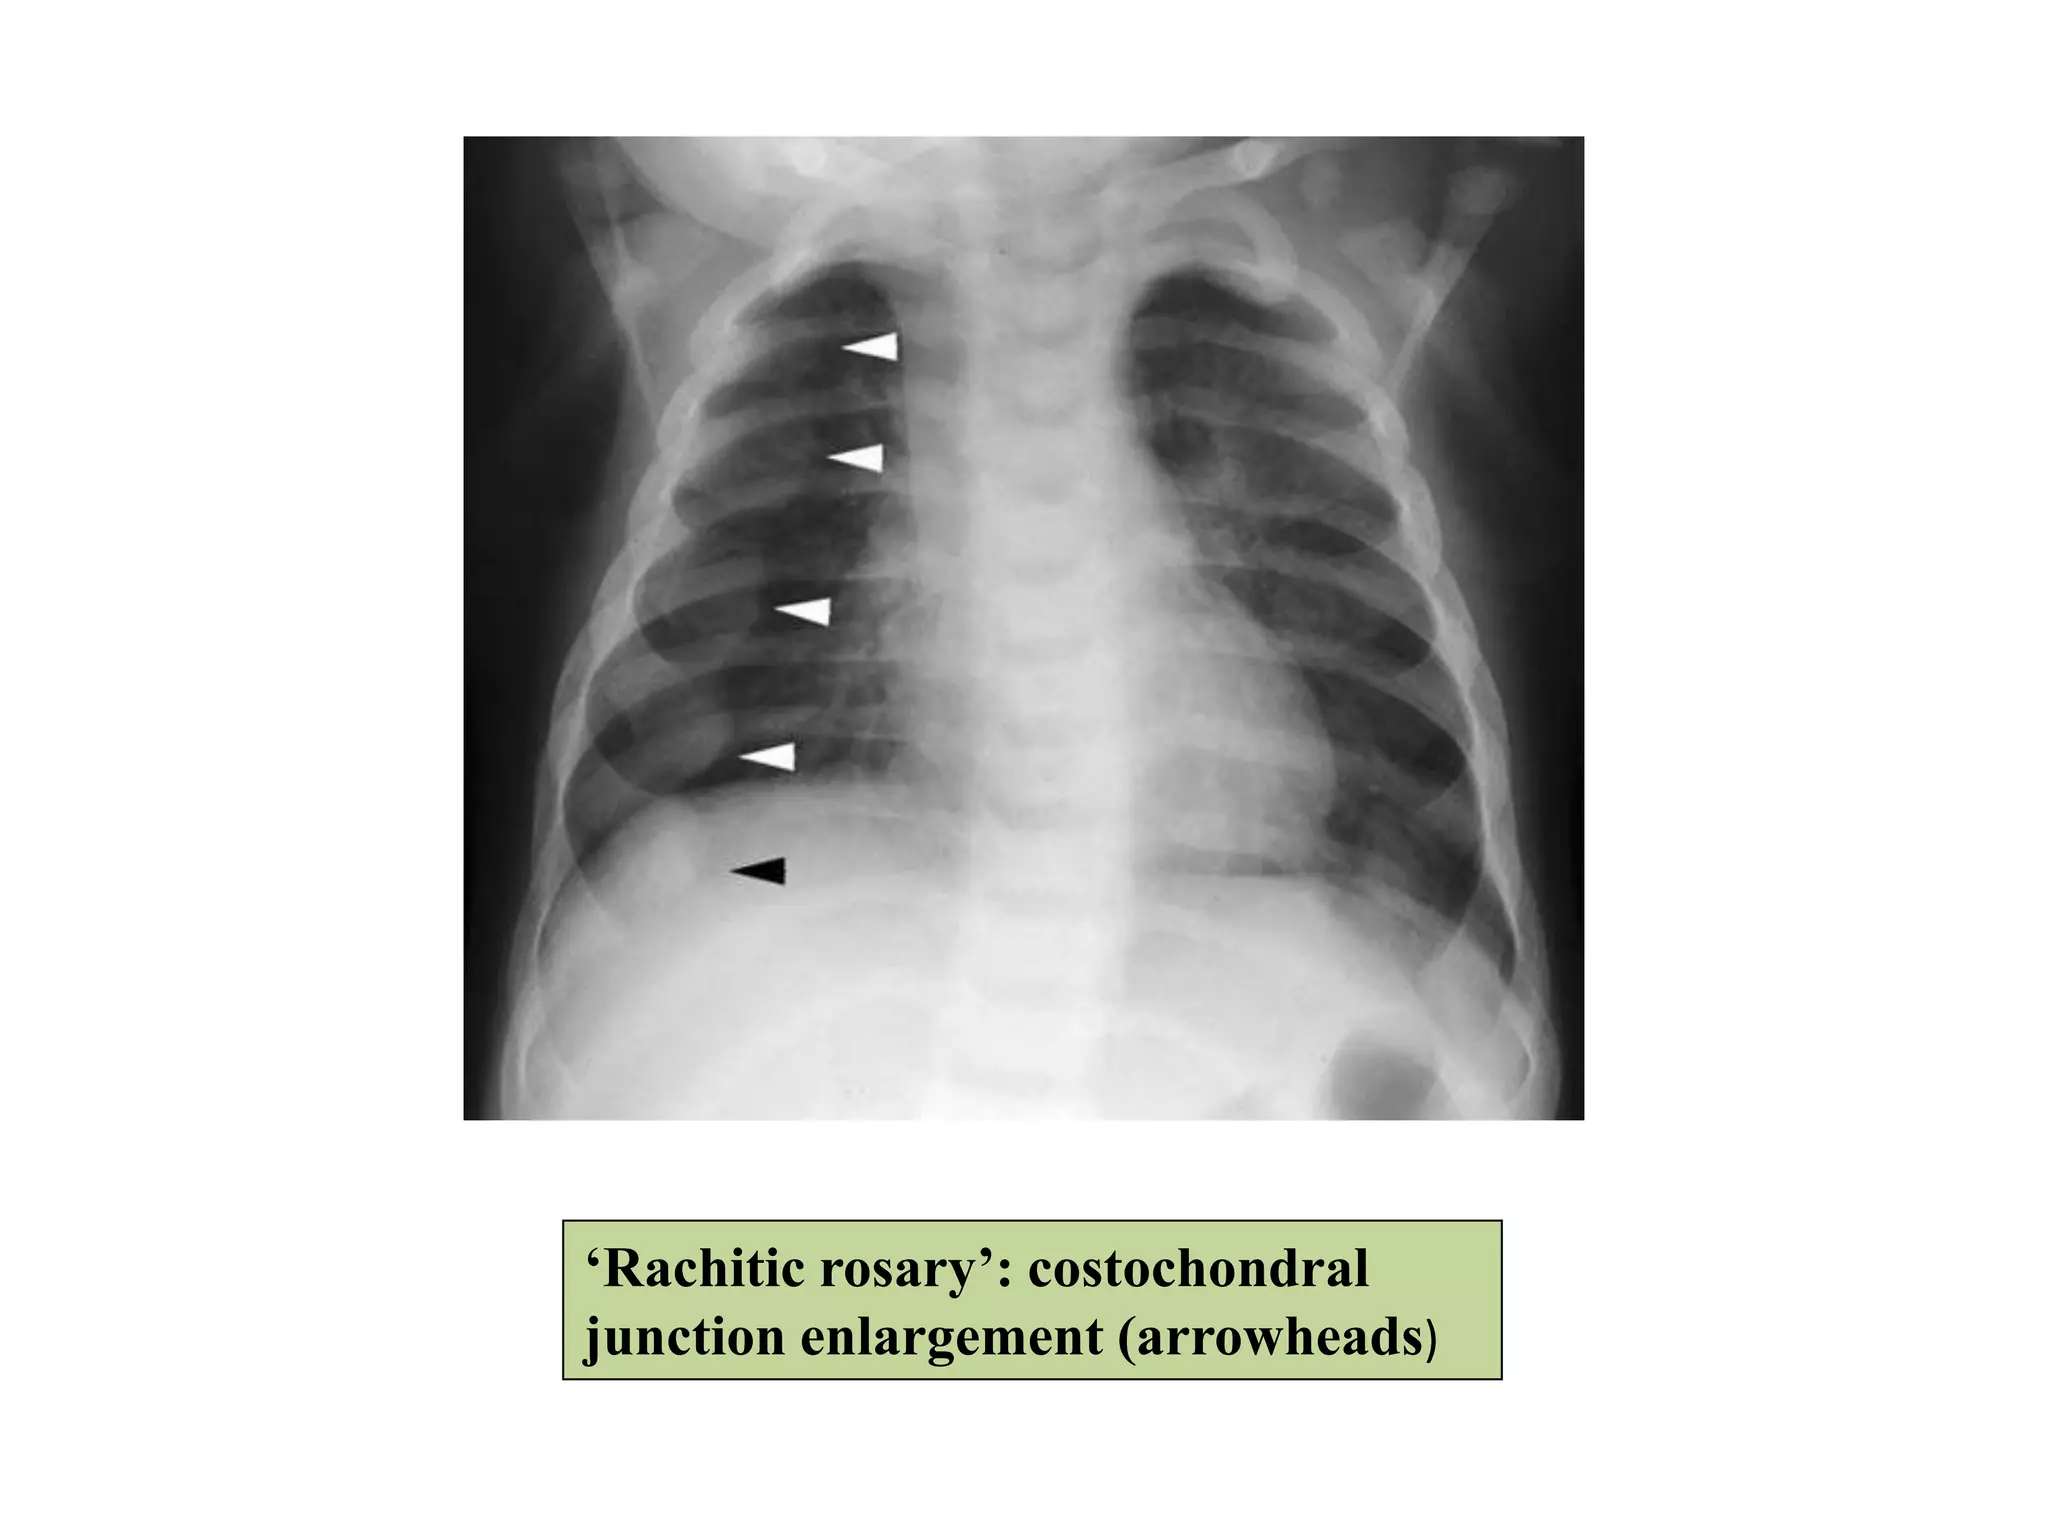

Changes in Thorax:

• Enlargement of growth plates at costochondral

junction---Rachitic rosary.

‘Rachitic rosary’: costochondral

junction enlargement (arrowheads)